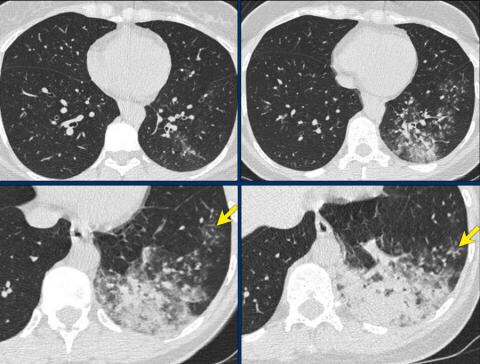

Examples of CO-RADS 3. Click to enlarge.

CORADS 3

COVID-19 unsure or indeterminate.

CT abnormalities indicating infection, but unsure whether COVID-19 is involved, like widespread bronchopneumonia, lobar pneumonia, septic emboli with ground glass opacities.

Case 1.

One day complaints. CT: Unifocal GGO. PCR negative.

Case 2.

CT: Unifocal GGO (circle).

Case 3.

CT: Unifocal GGO (arrow).

Case 4.